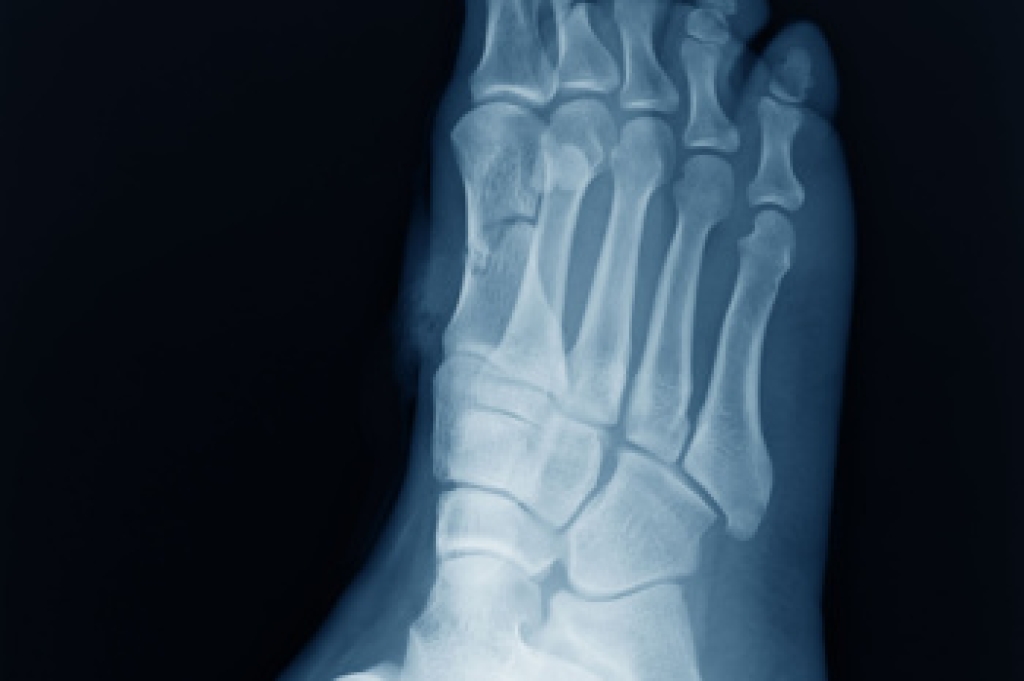

Diagnosis of cuboid syndrome is often difficult, and it is often misdiagnosed. X-rays, MRIs and CT scans often fail to properly show the cuboid subluxation. Although there isn’t a specific test used to diagnose cuboid syndrome, your podiatrist will usually check if pain is felt while pressing firmly on the cuboid bone of your foot.

Diagnosis

Due to the wide variety of potential causes of ankle pain, podiatrists will utilize a number of different methods to properly diagnose ankle pain. This can include asking for personal and family medical histories and of any recent injuries. Further diagnosis may include sensation tests, a physical examination, and potentially x-rays or other imaging tests.